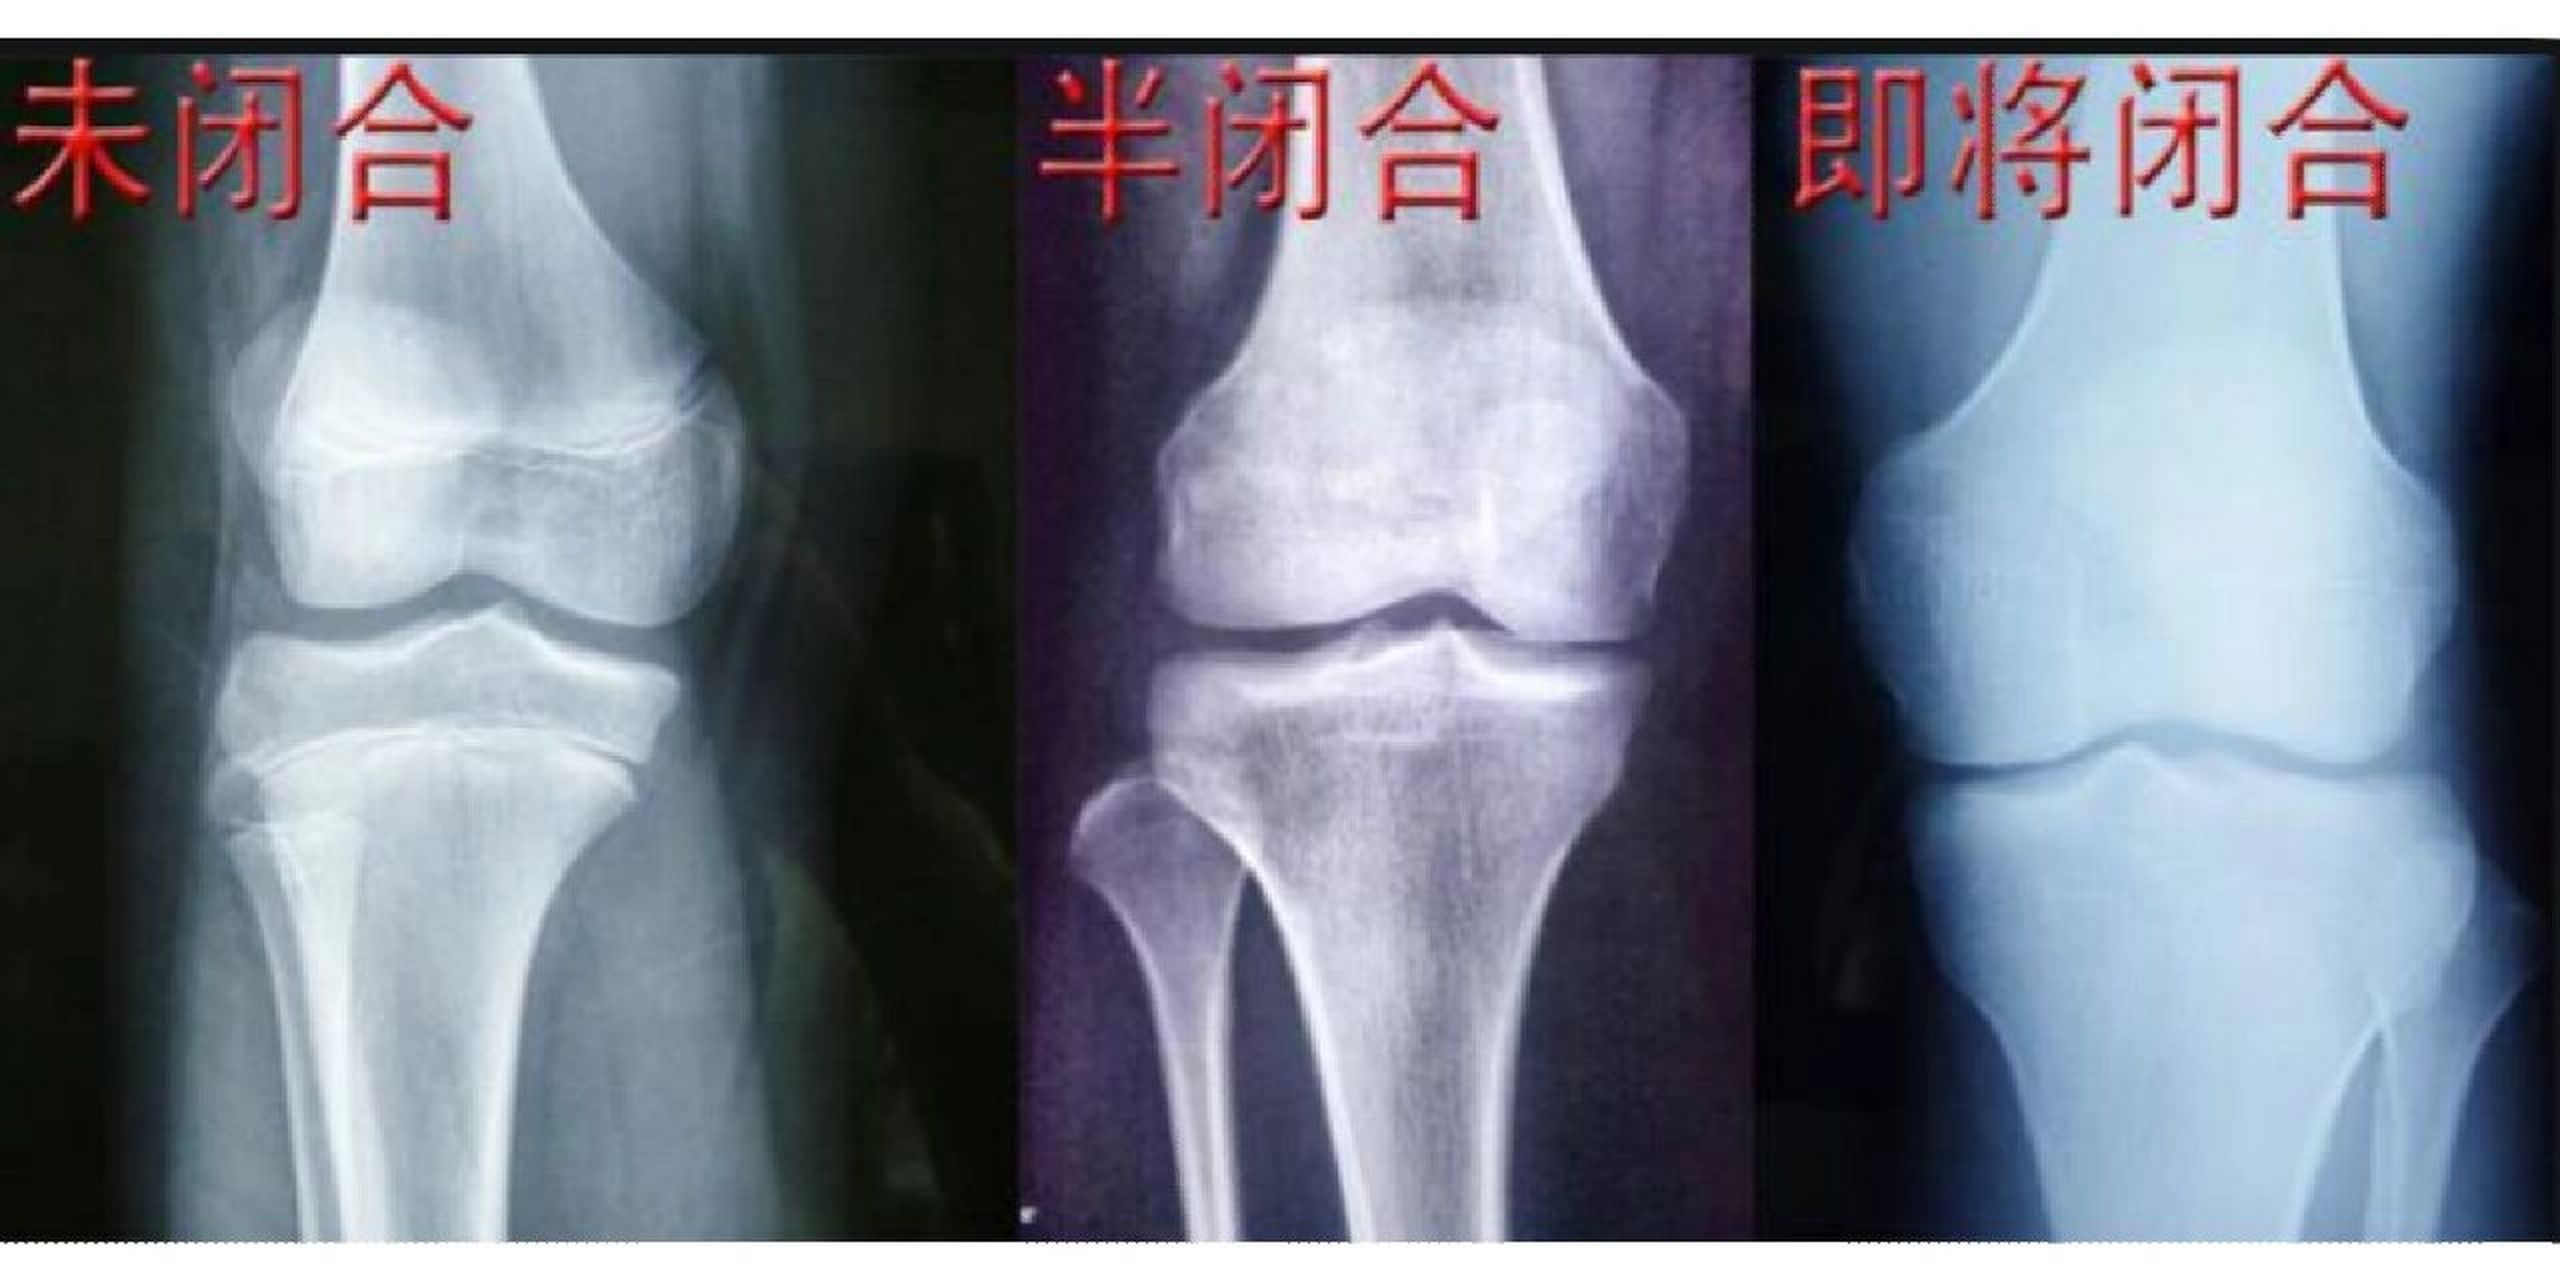

骨骺线对照图

到底怎么样才算是骨骺线真正的闭合吗?